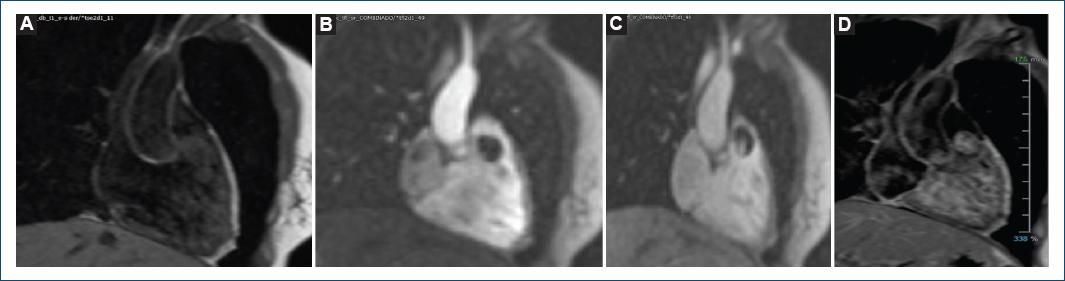

Figure 4 Cardiac magnetic resonance. CMR shows a well-defined, pedunculated mass, arising from de RVOT, occupying 80% of the RVOT, isointense on T1-weighted images. A: the mass has heterogeneous enhancement during the perfusion images. B and C: T1-weighted images after gadolinium. D: RVOT: right ventricular outflow tract.